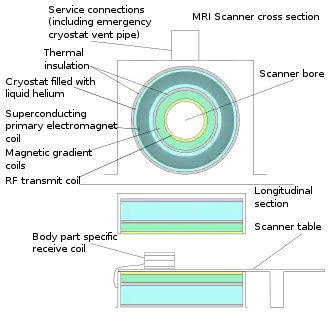

In most medical applications, hydrogen nuclei, which consist solely of a proton, that are in tissues create a signal that is processed to form an image of the body in terms of the density of those nuclei in a specific region. Given that the protons are affected by fields from other atoms to which they are bonded, it is possible to separate responses from hydrogen in specific compounds. To perform a study, the person is positioned within an MRI scanner that forms a strong magnetic field around the area to be imaged. First, energy from an oscillating magnetic field is temporarily applied to the patient at the appropriate resonance frequency. Scanning with X and Y gradient coils causes a selected region of the patient to experience the exact magnetic field required for the energy to be absorbed. The atoms are excited by a RF pulse and the resultant signal is measured by a receiving coil. The RF signal may be processed to deduce position information by looking at the changes in RF level and phase caused by varying the local magnetic field using gradient coils. As these coils are rapidly switched during the excitation and response to perform a moving line scan, they create the characteristic repetitive noise of an MRI scan as the windings move slightly due to magnetostriction. The contrast between different tissues is determined by the rate at which excited atoms return to the equilibrium state. Exogenous contrast agents may be given to the person to make the image clearer.[6]

The major components of an MRI scanner are the main magnet, which polarizes the sample, the shim coils for correcting shifts in the homogeneity of the main magnetic field, the gradient system which is used to localize the region to be scanned and the RF system, which excites the sample and detects the resulting NMR signal. The whole system is controlled by one or more computers.

MRI requires a magnetic field that is both strong and uniform to a few parts per million across the scan volume. The field strength of the magnet is measured in teslas – and while the majority of systems operate at 1.5 T, commercial systems are available between 0.2 and 7 T. Whole-body MRI systems for research applications operate in e.g. 9.4T,[7][8] 10.5T,[9] 11.7T.[10] Even higher field whole-body MRI systems e.g. 14 T and beyond are in conceptual proposal[11] or in engineering design.[12] Most clinical magnets are superconducting magnets, which require liquid helium to keep them at low temperatures. Lower field strengths can be achieved with permanent magnets, which are often used in "open" MRI scanners for claustrophobic patients.[13] Lower field strengths are also used in a portable MRI scanner approved by the FDA in 2020.[14] Recently, MRI has been demonstrated also at ultra-low fields, i.e., in the microtesla-to-millitesla range, where sufficient signal quality is made possible by prepolarization (on the order of 10–100 mT) and by measuring the Larmor precession fields at about 100 microtesla with highly sensitive superconducting quantum interference devices (SQUIDs).[15][16][17]